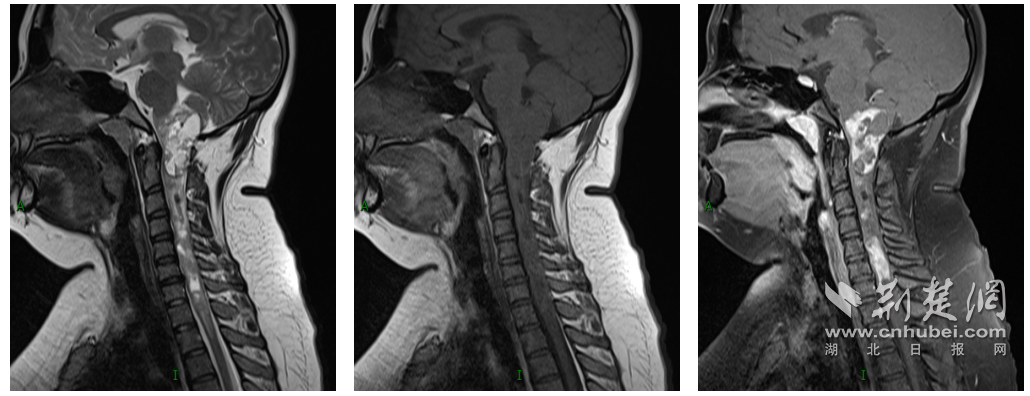

神经外科周迎春教授接诊后为小婷进行全面检查,发现她的肿瘤从脑干延髓一直向下生长至颈胸髓。延髓位于脑干下部,是控制呼吸心跳的“生命中枢”,各类神经和血管纵横交错,且肿瘤体积较大、串联生长(累及脑干-脊髓长度达15cm,其中延髓的病灶大小约5cm×4cm×2cm),导致周围脑干和脊髓组织严重受压,最窄的地方像纸片一样薄,在这样关键的解剖位置手术,犹如“刀尖起舞”,稍有不慎都有可能出现肢体瘫痪、呼吸心跳骤停等严重后果。但如不及时手术,任由肿瘤继续生长,持续压迫延颈髓,随时可能危及生命。

图为:术前MRI显示病灶从延髓向下串联、延伸至胸1椎体水平

图为:术后MRI显示病灶完整切除,正常延髓受压菲薄